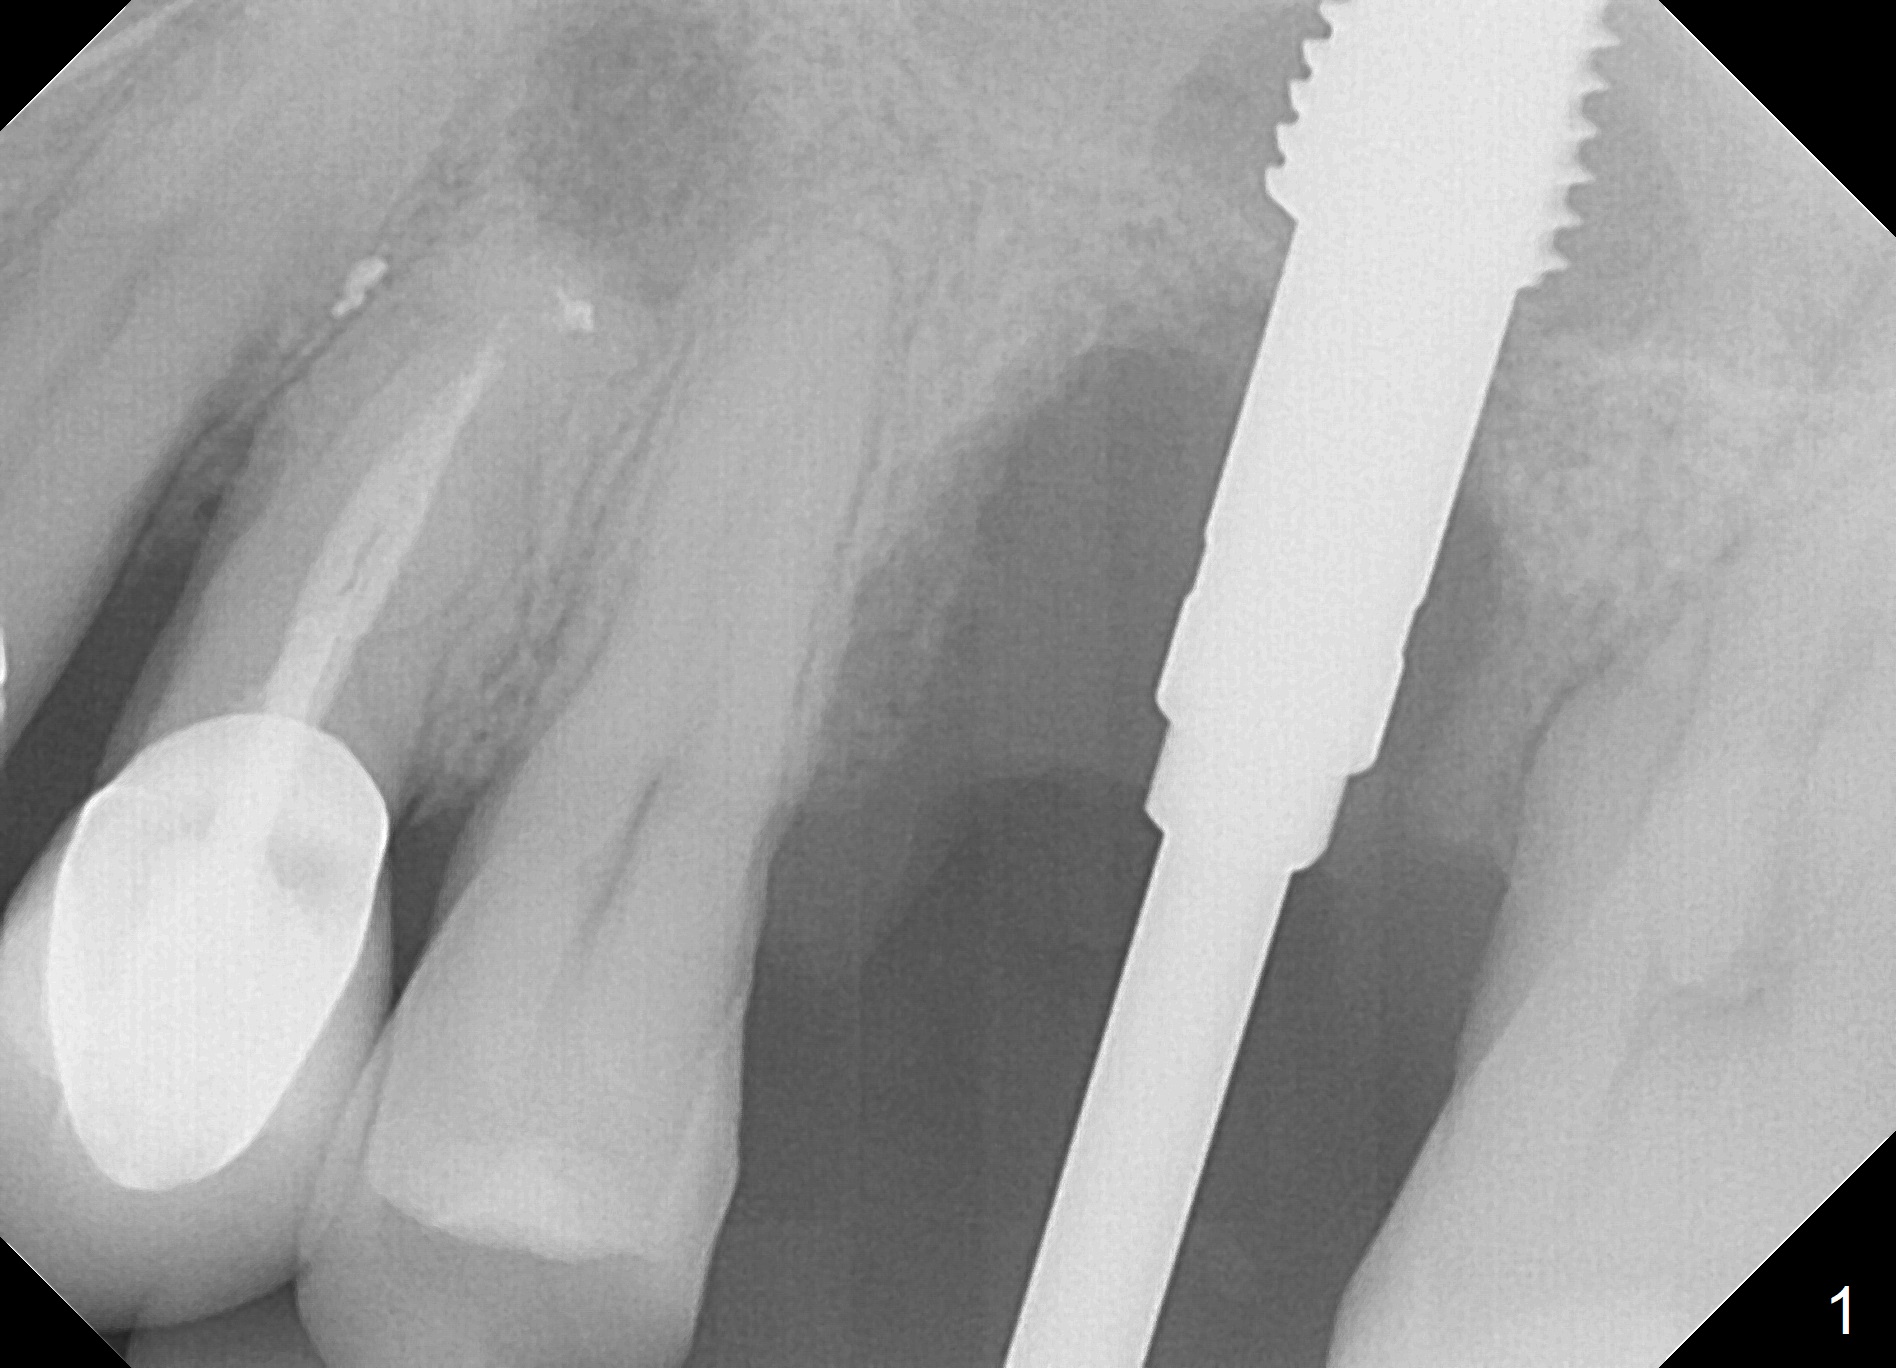

When the tooth #14 is extracted, the buccal plate is lost, while the apex of the palatal socket is perforated.  The palatal slope of the septum appears to be a suitable site for osteotomy, but the depth seems to be 2 mm.  After sequential osteotomy until 5.3 mm with drills, a 5.9 mm SM tap obtains stability (Fig.2).  A 5.9x8 mmm implant is placed with barely sufficient stability after 1 piece of PRF membrane and VeraGraft (Fig.2-4).  The implant rotates and dislodges when an abutment is being placed.  Neither do 6-8x17 mm Tatum taps achieve primary stability.  Socket preservation is performed, followed by periodontal dressing (Fig.5).  Primary stability might have been obtained if a smaller IBS implant with fins were placed in the palatal socket.  The periodontal dressing has dislodged 1 week postop; the socket appears healing (Fig.6,7).  Bone graft seems to be minimal or bone density of the graft is low (Fig.8).  The socket heals with a wide ridge 2 months post socket preservation, but the tooth #15 seems to be buccal (Fig.9) and mesial (Fig.10) shift.  After use of Magic Split and Expanders (until 3.8 mm for 13 mm), try 5 mm dummy implant (Fig.11).  If 6 mm one fails to achieve stability substantially, switch to 7 mm Tatum tapered tap provided there is enough mesiodistal space (use 8 mm implant positioner to gauze the space beforehand (preop)).  Consider using Vanilla (not Vera) Graft to fill in the gap between implant and osteotomy.  When primary stability is obtained, place a nonfunctional provisional to prevent further shifting (Fig.11 white outline).  After osteointegration, use the provisional (reline and separator) to distalize the tooth #15.